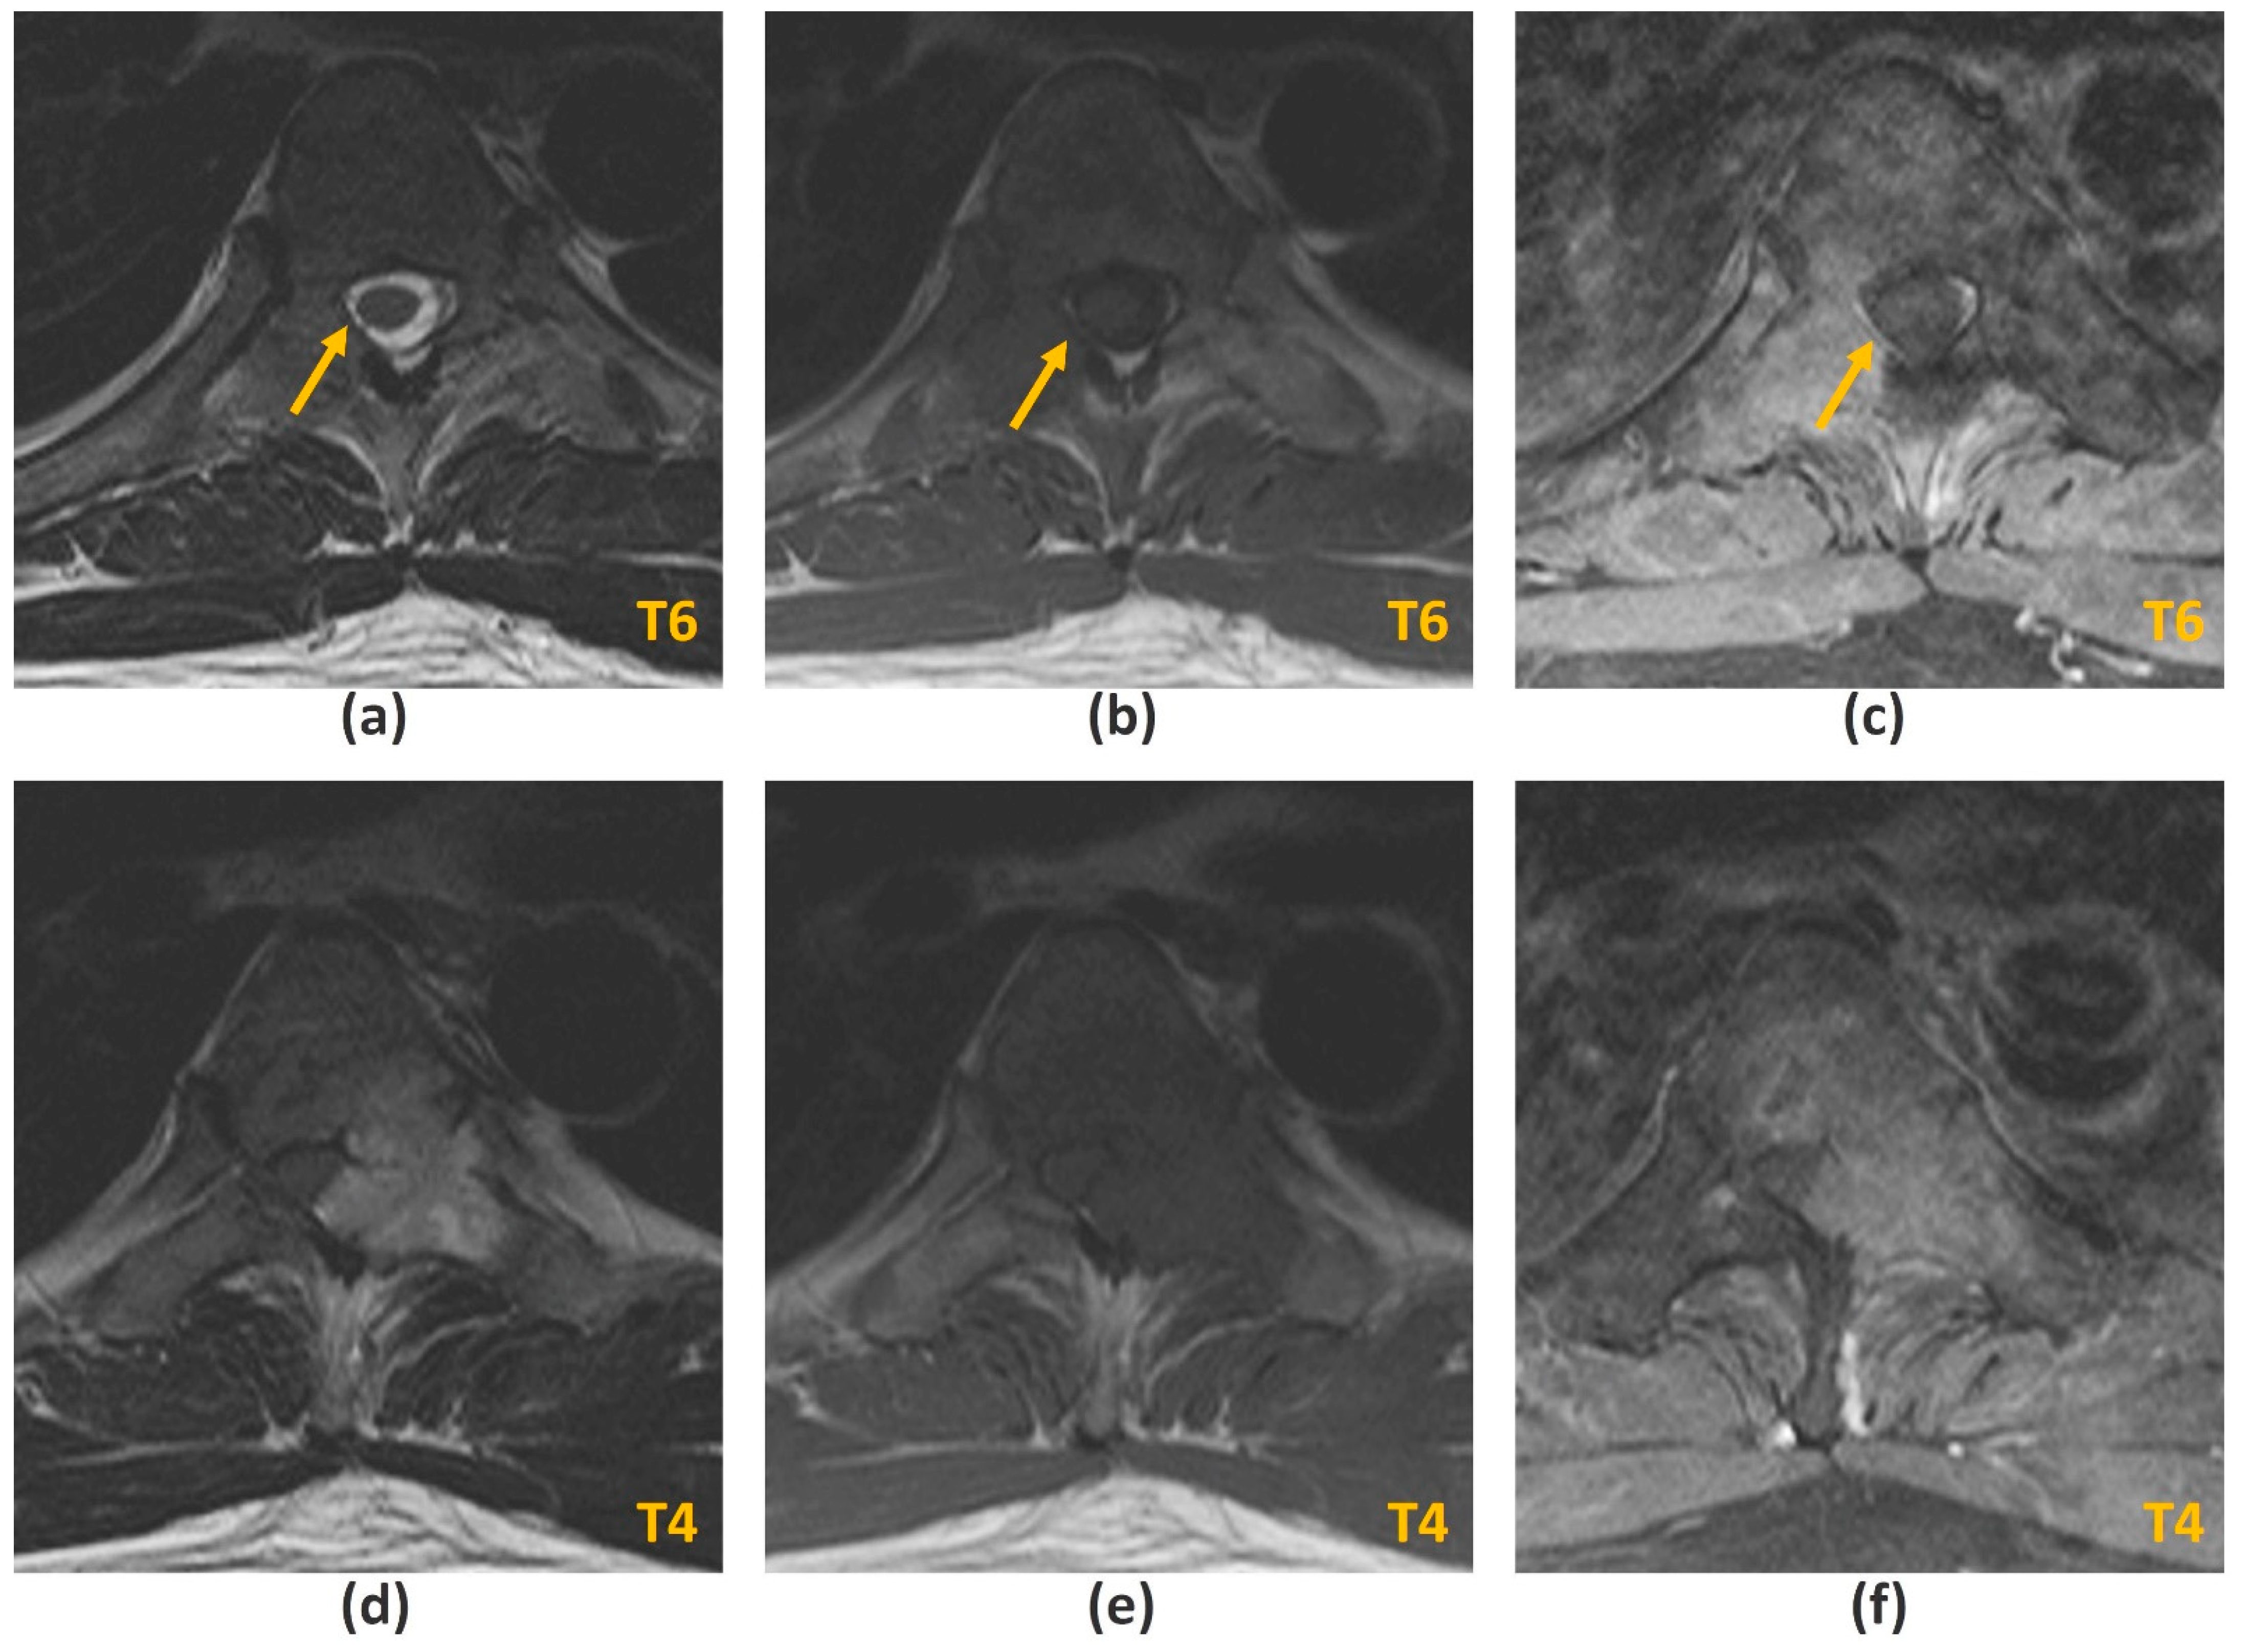

3.2.1. Challenges of MRI: Metal-Related Artifacts

- Stradiotti, P.; Curti, A.; Castellazzi, G.; Zerbi, A. Metal-related artifacts in instrumented spine. Techniques for reducing artifacts in CT and MRI: State of the art. Eur. Spine J. 2009, 18 (Suppl. 1), 102–108. [Google Scholar] [CrossRef]

- Krätzig, T.; Mende, K.C.; Mohme, M.; Kniep, H.; Dreimann, M.; Stangenberg, M.; Westphal, M.; Gauer, T.; Eicker, S.O. Carbon fiber-reinforced PEEK versus titanium implants: An in vitro comparison of susceptibility artifacts in CT and MR imaging. Neurosurg. Rev. 2021, 44, 2163–2170. [Google Scholar] [CrossRef]

- Jungmann, P.M.; Agten, C.A.; Pfirrmann, C.W.; Sutter, R. Advances in MRI around metal. J. Magn. Reson. Imaging 2017, 46, 972–991. [Google Scholar] [CrossRef]

- Kumar, N.; Lopez, K.G.; Alathur Ramakrishnan, S.; Hallinan, J.T.P.D.; Fuh, J.Y.H.; Pandita, N.; Madhu, S.; Kumar, A.; Benneker, L.M.; Vellayappan, B.A. Evolution of materials for implants in metastatic spine disease till date—Have we found an ideal material? Radiother Oncol. 2021, 163, 93–104. [Google Scholar] [CrossRef] [PubMed]

- Kumar, N.; Ramakrishnan, S.A.; Lopez, K.G.; Madhu, S.; Ramos, M.R.D.; Fuh, J.Y.H.; Hallinan, J.; Nolan, C.P.; Benneker, L.M.; Vellayappan, B.A. Can Polyether Ether Ketone Dethrone Titanium as the Choice Implant Material for Metastatic Spine Tumor Surgery? World Neurosurg. 2021, 148, 94–109. [Google Scholar] [CrossRef] [PubMed]